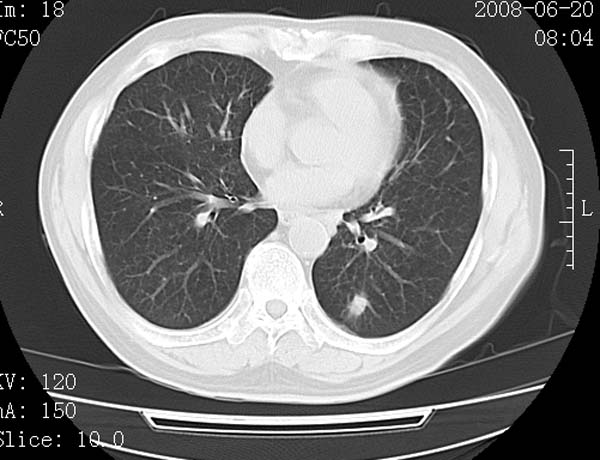

以下是引用守望可可西里在2008-6-24 1:11:00的发言:[br][br] 考虑为周围型肺癌:[br] 1.分叶结节,形态极不规则,蟹足样伸展的恶性浸润特征比较明确。[br] 2.磨玻璃影中由多个更高密度小结节聚集呈梅花瓣样。[br] 3.局部胸膜凹陷征比较明确。[br][br] 另:纵隔胸膜明显增厚、粘连。

以下是引用zjzjr在2008-6-24 11:19:00的发言:[br]支持左下肺周围型肺癌伴右肺转移,纵隔淋巴结转移,心包积液.

以下是引用zhangling在2008-6-24 14:56:00的发言:[br]我们科室意见报告为[br][br]1考虑左下肺周围型肺癌[br]2右肺小结节考虑转移瘤,纵隔淋巴结转移[br]3心包积液. [br] 各位老师分析的相当好 谢意[br]